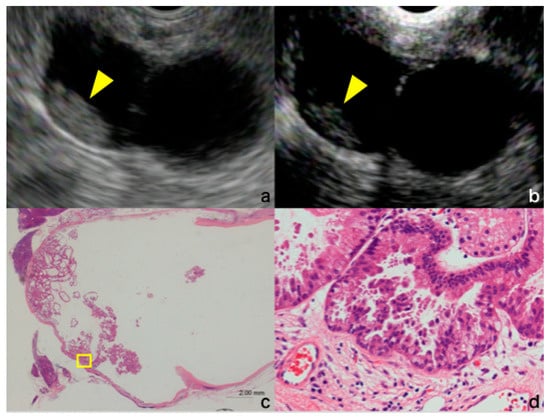

- Kamata, K.; Kitano, M. Endoscopic diagnosis of cystic lesions of the pancreas. Dig. Endosc. 2019, 31, 5–15. [Google Scholar] [CrossRef]

- Harima, H.; Kaino, S.; Shinoda, S.; Kawano, M.; Suenaga, S.; Sakaida, I. Differential diagnosis of benign and malignant branch duct intraductal papillary mucinous neoplasm using contrast-enhanced endoscopic ultrasonography. World J. Gastroenterol. 2015, 21, 6252–6260. [Google Scholar] [CrossRef]

- Kitano, M.; Sakamoto, H.; Komaki, T.; Kudo, M. New techniques and future perspective of EUS for the differential diagnosis of pancreatic malignancies: Contrast harmonic imaging. Dig. Endosc. 2011, 23 (Suppl. 1), 46–50. [Google Scholar] [CrossRef]

- Yamashita, Y.; Ueda, K.; Itonaga, M.; Yoshida, T.; Maeda, H.; Maekita, T.; Iguchi, M.; Tamai, H.; Ichinose, M.; Kato, J. Usefulness of contrast-enhanced endoscopic sonography for discriminating mural nodules from mucous clots in intraductal papillary mucinous neoplasms: A single-center prospective study. J. Ultrasound Med. 2013, 32, 61–68. [Google Scholar] [CrossRef]